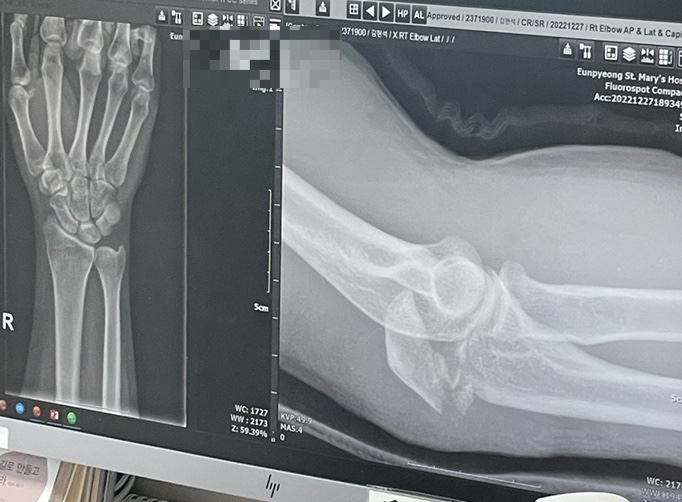

안녕하세요, 헤니예요 ? 22년12월27일부터 23년까지는 저한테 참 힘든 때 였어요. 신랑이 먼저 팔꿈치골...

은평성모병원 팔꿈치 플레이트제거, 그리고 신경이전술까지

이전포스팅 입니다. ? 드.디.어 22년 12월 27일에 다친 팔꿈치 거의 1년 6개월만에 잡힌 핀 제거의 일정...